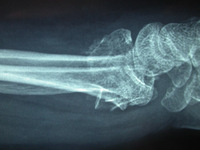

Fratura intra-articular do tipo B (simples) do rádio distal: vista lateral

Do acervo do Dr. Chaitanya S. Mudgal